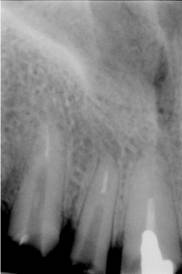

La nivelul lui 12 si 13 se observa obturatia de canal corect executata din punct de vedere radiologic. Clinic se constata obturarea canalelor radiculare cu ciment oxifosfat de zinc si fara con de gutaperca. Pe a doua radiografie se observa dezobturarea corecta a canalelor radiculare pt. realizarea unor DCR-uri.